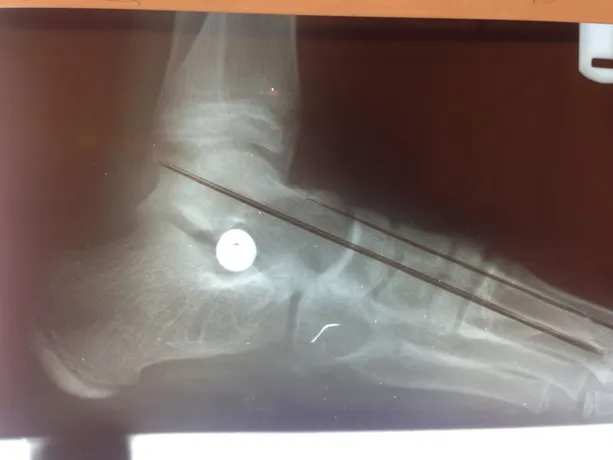

Pre and Postop X-rays Subtalar Joint Implant (Below)

Pre and Postop Subtalar Implant and Percutaneous Achilles Lengthening Below. The first pics show wedging of the distal tibia physis causing ankle valgus due to constant pressure caused by the severity of the flatfoot (JT)